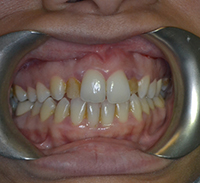

At Gramercy Smiles we are dedicated to creating lasting smiles through comprehensive care using the latest technology. We proudly offer personalized, patient-driven care focused on the health, beauty, and functionality of your teeth. Please browse our smile gallery below and contact us to schedule a smile consultation today.